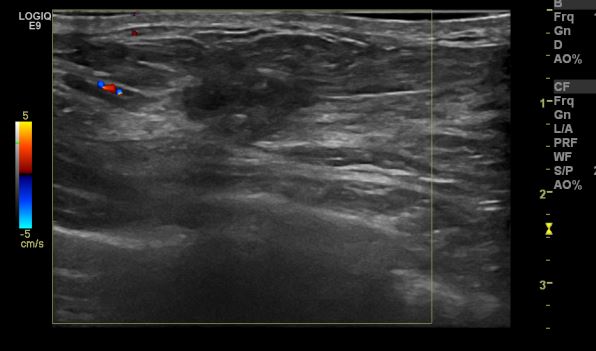

건강검진상 이상 소견으로 내원하신 40대 여성분으로 우측 유방 10시 30분  방향에

으심스러운 멍울 조직검사 시행하여 우측 침윤성 유관암 진단 되었습니다.